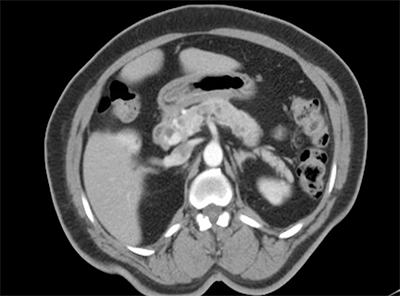

Following the left nephrectomy, the patient was asymptomatic—without abdominal pain or other symptoms of pancreas disease. The patient and her doctors chose to continue close monitoring with ultrasound or MRI imaging performed every six months for surveillance. No significant changes were noted until age 55, when an asymptomatic mass was first noted in the pancreas head. During the next 18 months this mass increased in size to 3 cm and she was referred to us (Figure 1).

Figure 1. CT abdomen demonstrating 2.9 x 2.7 cm enhancing mass in the pancreatic head, multiple cystic structures within the pancreas for which intraductal papillary mucinous neoplasm is not excluded.